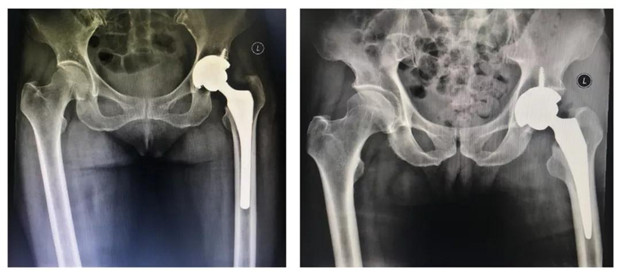

股骨颈骨折

人工全髋关节置换术后